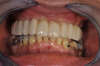

AVANT

La patiente présentait des dents non conservables. 6 implants ont été mis en place avec la réalisation d'une prothèse fixe qui remplace toutes les dents. Grâce aux implants, la patiente a retrouvé la confiance en soi. Elle peut manger et sourire.